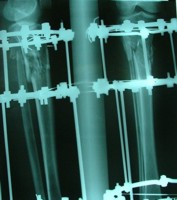

قطعات الیزاروف:

الیزاروف دارای عناصر اولیه و عناصر ثانویه است:

Bolt slotted-pin-ringعناصر اولی:

ها را به هم وصل می کند. .ringعناصر ثانویه: تمام قطعاتی که

پین ها باید در دو طرف رینگ گذاشته شود تا رینگ تاب نخورد،واشر کونیکال یا اسفریکال واشر تا 5/7(نیست به رینگ) درجه زاویه به راد می دهد .

باکل:وسیله ای که روی رینگ می چرخد                                            رینگ اومگا:برای بالای بازو و (یاهومروس)

rodیاpostفراموش نشود: استفاده از واشر شیار دار زیر

برای فیکس یک قطعهrodفراموش نشود  استفاده ا ز  واشر شیار  دارد در وسط

وایر ا لیزاروف  باسر بایونت(سوراخ کردن دیافیز) و تروکار(سوراخ کردن متافیز داپی فیز- سر پهن دارد)

-مقدار کشش وایر بین 130تا50 کیلوگرم است .

-  اگر نتوان دهانه تنشنر را روی رینگ گذاشت باید بین آنها یک سوکت قرار داد .

- مکعب رزوه دار برای نصب پین در زاویه های مختلف هم مفید است .

-در زاویه های مختلف هم مفید است .shan2مکعب رزوه دار برای نصب -

نیز مفید است که می توان روی مکعب روزه دار نیز وصل شود .drop wire- استفاده از هالف پین به جای